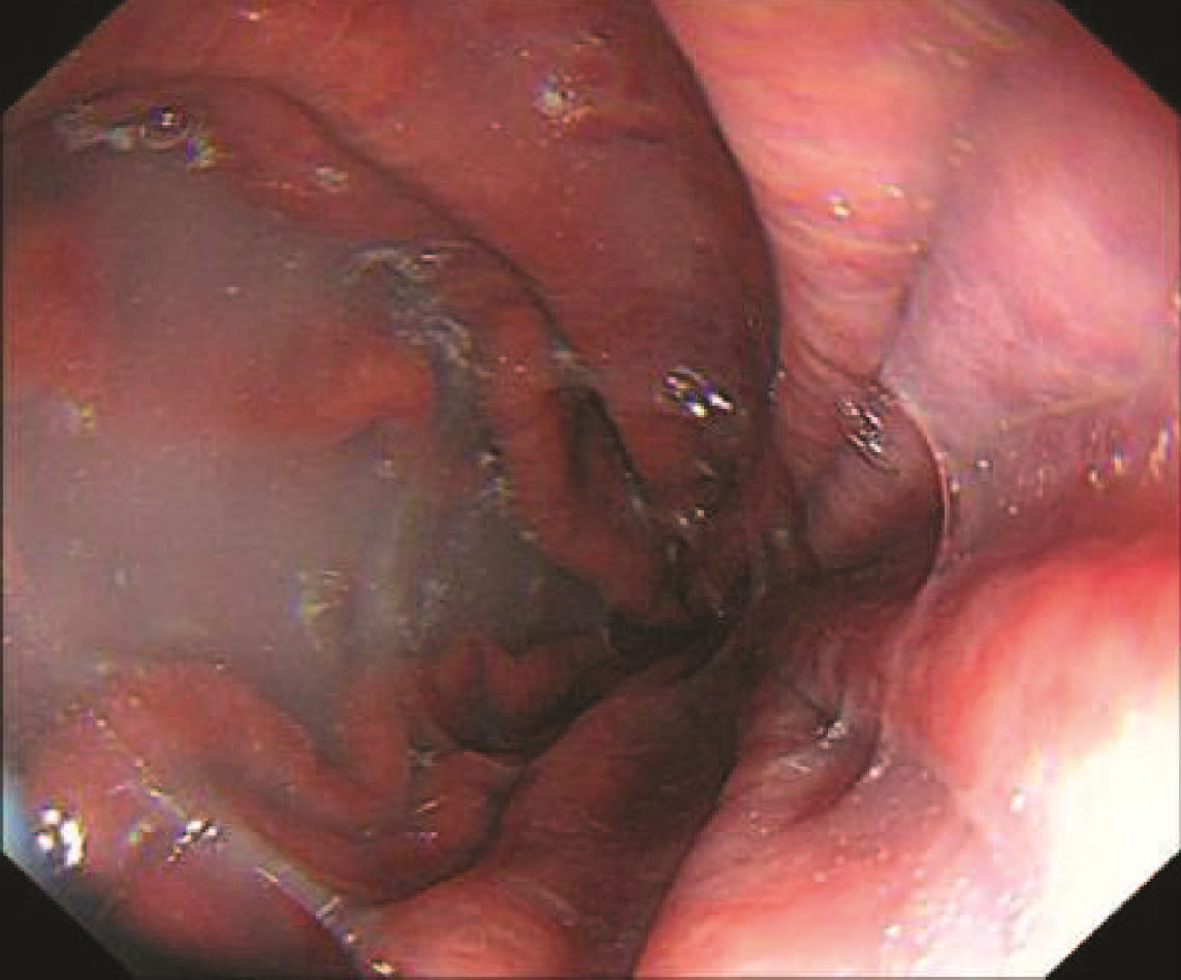

Endoscopic sequential ligation for treatment of esophageal and gastric varices with duodenal varices: A case report

Hao WEN, Zhaohui HE, Tong JIANG, Guoqing SHI

2023, 39(3): 637-639. DOI: 10.3969/j.issn.1001-5256.2023.03.024

Abstract(837) HTML (263) PDF (2676KB)(95)

Abstract: